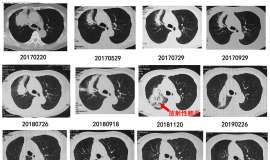

妻子确诊7年了。回想当年确诊时一家人惊恐哀伤的情状犹历历在目,一回首已走过2000多个日日夜夜,心中能不感慨万千! 幸运的是妻子确诊后服用的易瑞沙至今一直有效,皮疹甲沟炎腹泻等副作用也不大,肝 ...